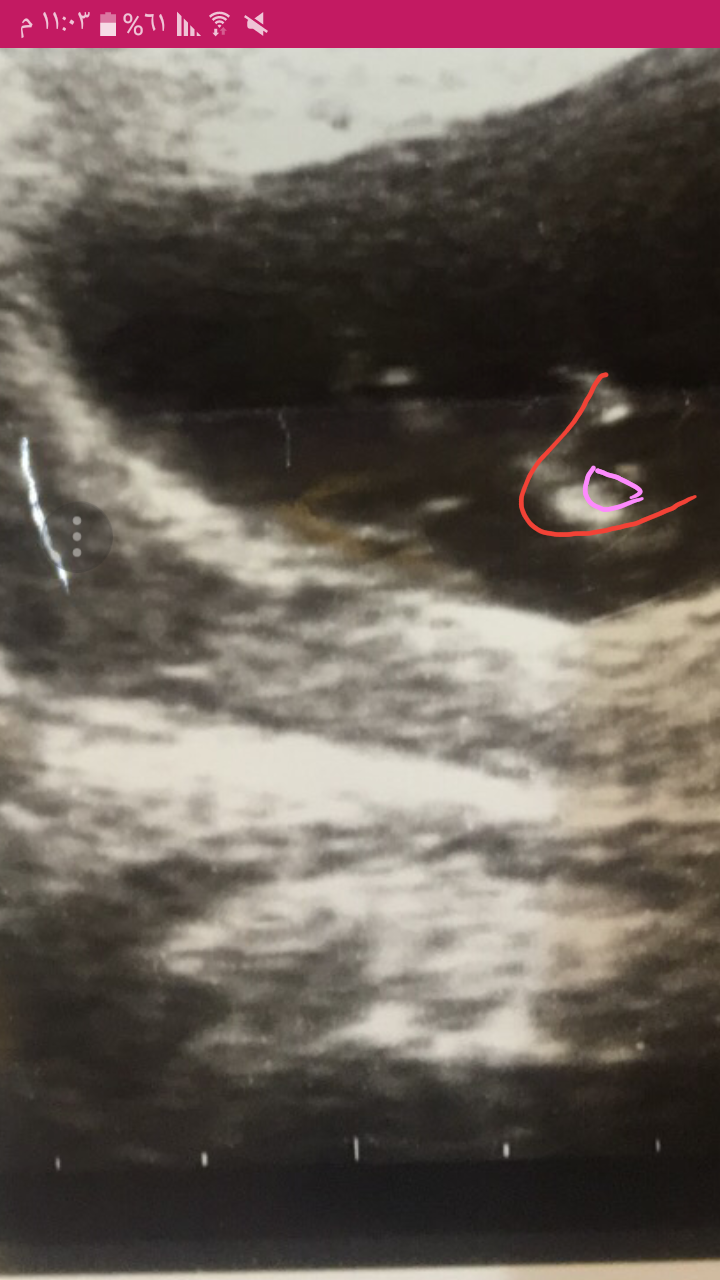

عزيزتي اذا الله ما اخطاني الجنين بنت 80 % طبعا استنادا على التوضيح الدائره الزهري مكان عضو التناسلي وباين انه 3 خطوط اثنين ابيض والثالث بالمنتصف اسود. والله اعلى واعلم. وربنا يرزقك ما تتمني